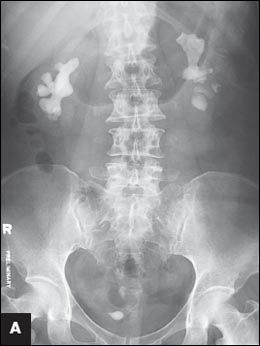

Figure 1 – A pretreatment plain radiograph reveals bilateral renal stones and a right lower ureteral stone inside an ureterocele (

A

). Treatment results are shown after the first percutaneous nephrolithotomy (PCNL) and removal of the ureteral stone (

Urinalysis showed 5 to 10 white blood cells and 3 to 5 red blood cells per high-power field. Urine culture was negative. Plain radiography with a kidney-ureter-bladder (KUB) view revealed multiple opacities in the region of both kidneys and specifically in a location that corresponded to each renal pelvis (Figure 1A). A subsequent intravenous urogram (IVU) confirmed the presence of bilateral renal staghorn calculi and a right ureteral stone within a ureterocele. A radioisotopic study showed the differential function of the right and left kidneys to be 44% and 56%, respectively, with scarring in the upper pole of the right kidney. Serum calcium, phosphate, urate, blood urea nitrogen, creatinine, and electrolyte levels were normal.